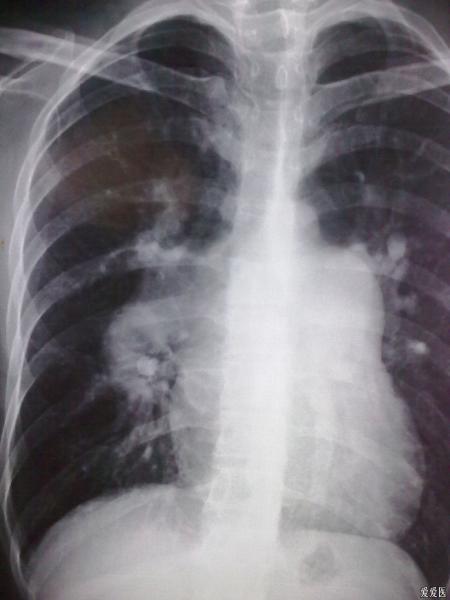

典型肺动脉高压胸片(室间隔缺损)

1、肺动脉段突出。2、肺血管纹理变少了。3、右心室大,心尖圆钝。。